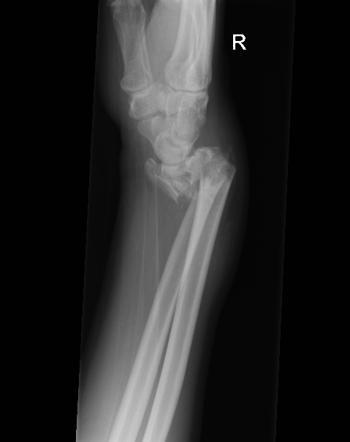

What is this?

Smith’s fracture

Distal radius fracture with volar (anterior) displacement of fracture fragments